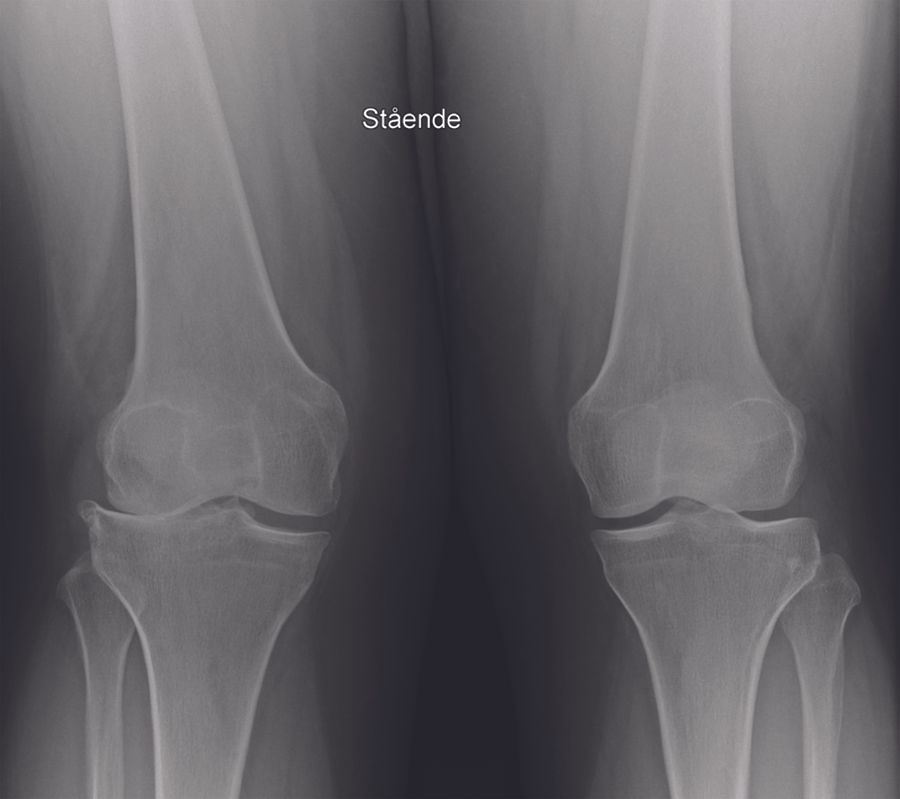

The clinical articles in this issue span knee reconstruction and surgical history. Topics include knee cartilage repair, acetabular reconstruction using a Kerboull-Tanaka reinforcement device, the indications for patellar resurfacing, and preoperative planning for fixed bearing lateral unicompartmental knee arthroplasty. A historical contribution examines Robert Merle d'Aubigné and the Judet brothers, contextualizing the foundational contributions that shaped modern orthopedic surgical practice.